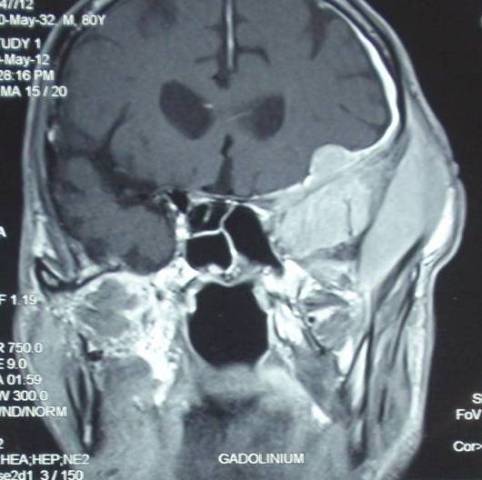

An 80-year-old male presented with headache and swelling over left temporal region since six months. Patient also complains of left retro-orbital pain. Contrast enhanced computerized tomography (CECT) revealed a large lobulated enhancing soft tissue density mass lesion measuring 37x28x72mm in the left infratemporal region extending intracranially into the basitemporal region and orbital apex on the left side and left periinsular region. There was evidence of destruction of superior wall of left orbit and left temporal bone with periosteal new bone formation and cortical destruction. Magnetic resonant imaging (MRI) revealed a lobulated T2 hyperintense and T1 iso-hypointense lesion centered in left sphenoid triangle with extension into left temporal fossa, inferior orbital fissure, left cavenus sinus, middle cranial fossa as well as with lateral zygomatic, subcutaneous and ethmoid sinus extension (Figure 1). Radiological possibility of malignant neoplasm of bone was suggested and patient was referred for FNAC from the palpable swelling in the left temporal region.

Figure 1- Magnetic resonant imaging (MRI) showing a lobulated lesion in the left sphenoid triangle with extension into left temporal fossa, inferior orbital fissure, left cavernous sinus, middle cranial fossa as well as with lateral zygomatic, subcutaneous and ethmoid sinus extension